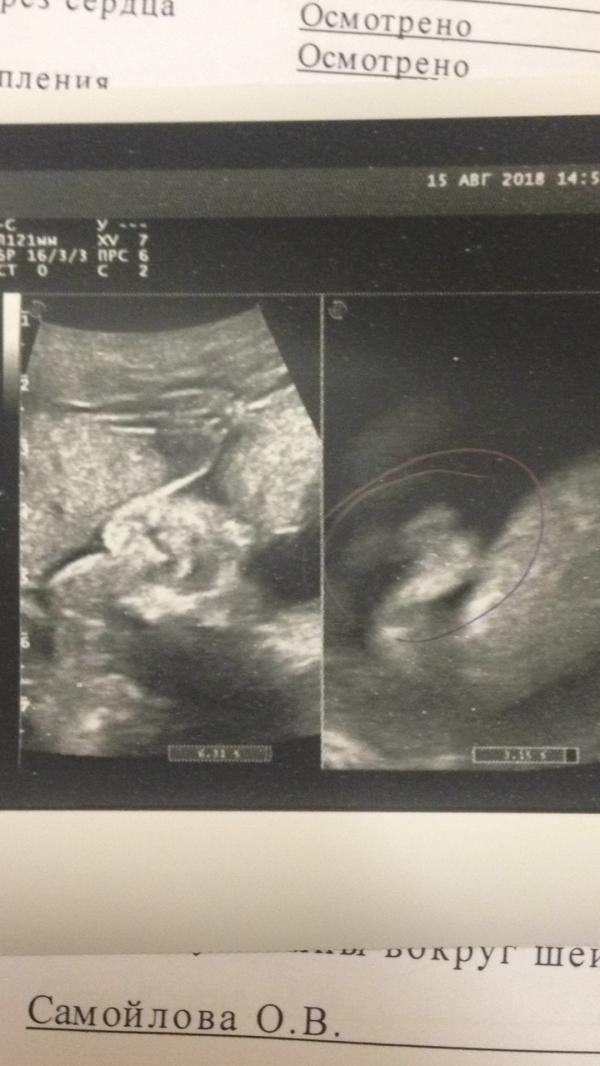

У кого такое было???может кто по УЗИ чего увидит опытным глазом..

Все детки сами нас выбирают... ваша крошка доверилась именно вам. Совсем скоро вы не будете представлять жизни без неё)) на УЗИ очень четко видно, что у вас девочка. Я вот с первой дочкой ещё не наигралась по-полной в принцесс и наряды....хотела бы ещё дочку))) но пока у мужа волосы на голове встают от таких моих мыслей)))

Ну я писюна не вижу